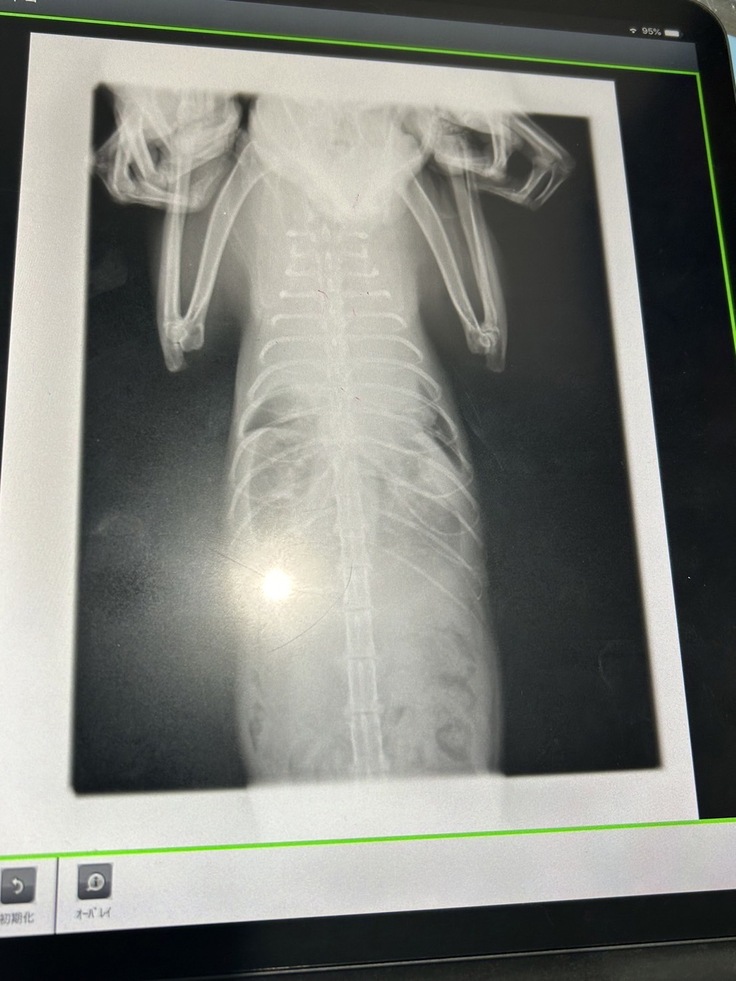

2/8 血液検査、レントゲン

2/22 血液検査、レントゲン、胸水60cc

3/7 血液検査、レントゲン、胸水90cc

3/14 血液検査、レントゲン、胸水140cc

3/21 血液検査、レントゲン、胸水160cc

3/28 レントゲン、胸水125cc

4/7 血液検査、レントゲン、胸水125cc

4/14 胸水197cc

胸部、水が溜まっている所が白濁しています

3月に入ると、水が溜まる頻度、量が増え始め、2週間毎の通院を1週間毎にした方が良いと獣医師から言われました。

また、点滴の量が肺に溜まる水量に大きく影響する為、利尿剤の薬と伴わせながら合間を取る治療がこの先も続きます。